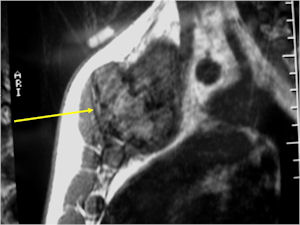

- There may be expansion of bone, cortical thinning and cortical breakthrough. A soft tissue mass may accompany this lesion but the soft tissue component is usually contained by the periosteum.

- The periosteum remains intact around the soft tissue component. Might need a CT scan to detect the subtle calcification (Egg Shell Rim of Calcification) associated with an intact periosteal reaction

CT Scan:

- More useful for detecting mineralization and evaluating extent of bone destruction than plain X-ray

MRI:

- Also useful in determining extent

- There is often extensive edema around the tumor in the surrounding bone and soft tissues that can lead to a misdiagnosis of a malignant tumor.